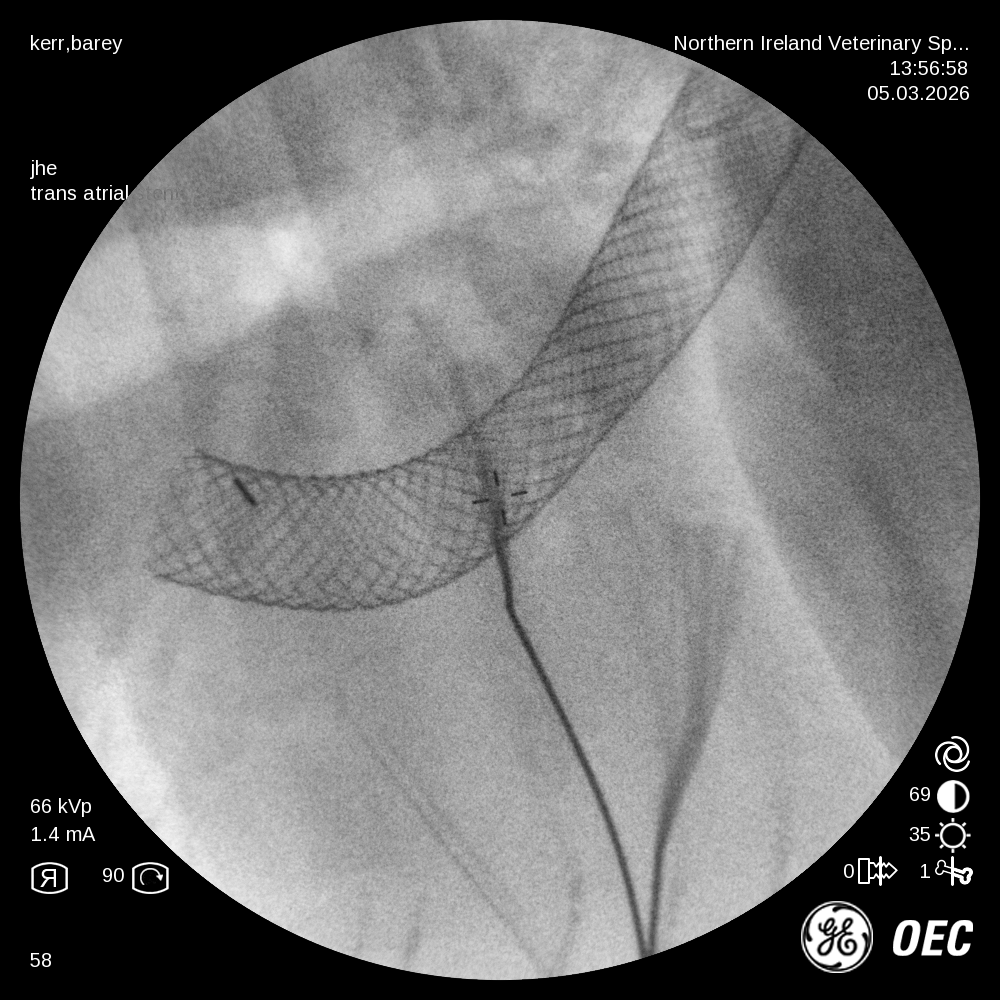

The minimally invasive, fluoroscopic-guided procedure involved accessing both the right jugular and left femoral veins. The location and extent of the mass was first determined by a contrast angiographic study. A series of catheters and guidewires were then used to deploy a woven Nitinol stent extending from the caudal to the cranial vena cava, through the right atrium. Repeat angiography revealed improved caudal vena caval flow and Barney recovered uneventfully. He was discharged the following morning.

Barney returned 2 weeks later for routine re-evaluation. His ascites had completely resolved and he was back to his normal self. Thoracic radiographs confirmed the stent remained in a stable position.